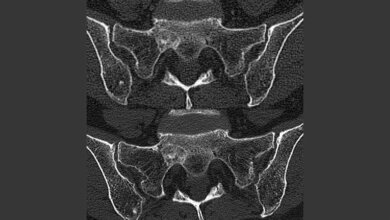

Für ihre Untersuchungen von Struktur und Zusammensetzung der Mikroumgebung des Knochens setzte das Potsdamer Forscherteam eine Reihe hochauflösender bildgebender Verfahren ein: Mikrocomputertomografie zur Untersuchung der Knochenarchitektur, Raman Imaging zum Scannen der chemischen Knochenspektren, Röntgenkleinwinkelstreuung (SAXS) zum Aufdecken der mineralischen Knocheneigenschaften. Hauptsächlich kam das Verfahren der dynamischen Histomorphometrie zum Einsatz, bei dem fluoreszierende Farbstoffe in verschiedenen Intervallen in den Knochen eingebracht werden. Dadurch werden Zeitstempel erzeugt, die die Geschwindigkeit der Knochenbildung zeigen.